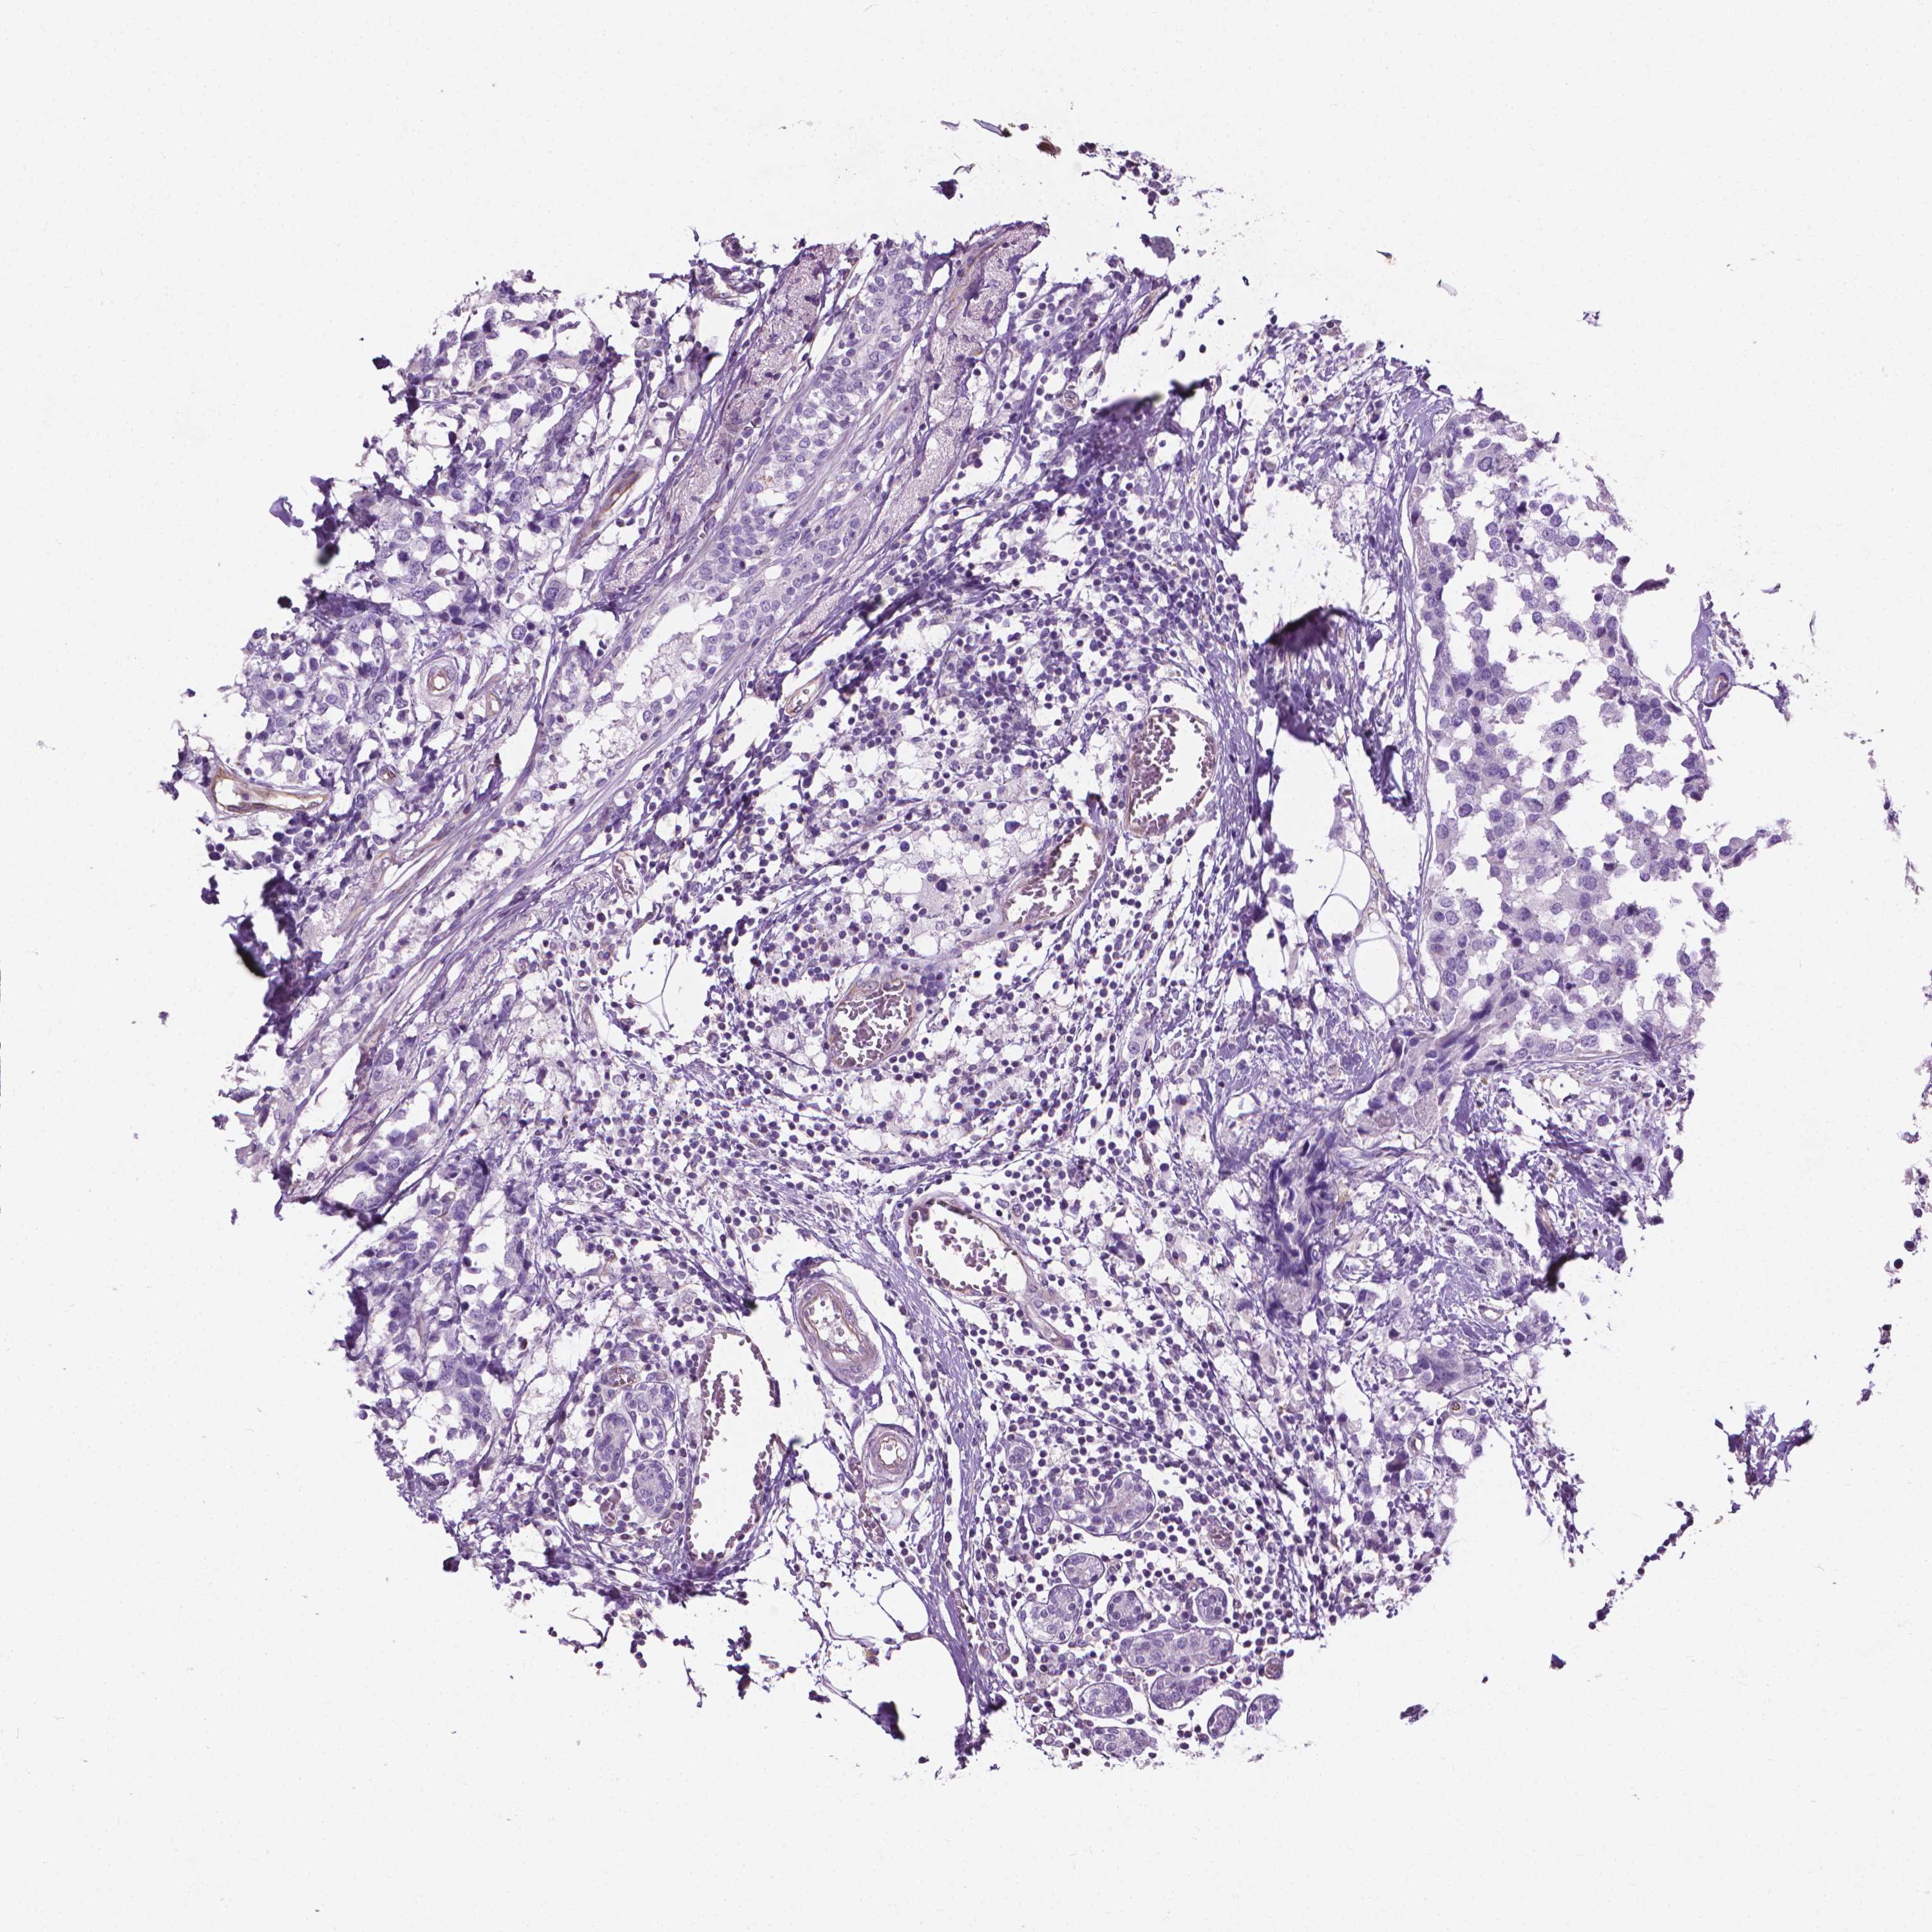

BRCA TCGA BRCA VALIDATION PROTEIN EXPRESSION